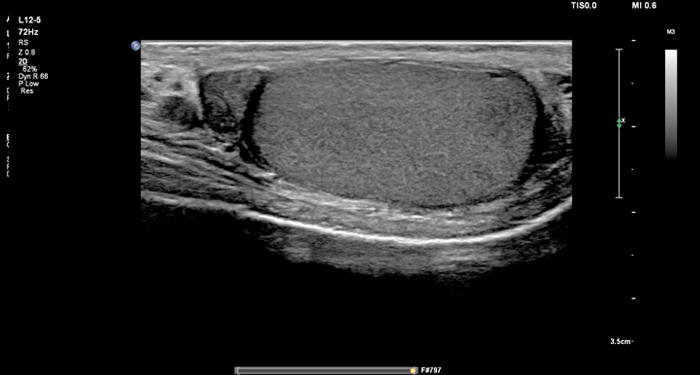

At the touch of a button, the new MaxVue high-definition display brings extraordinary visualisation of anatomy with 1,179,648 additional image pixels compared to a standard 4:3 display format mode. MaxVue enhances ultrasound viewing during interventional procedures and provides 38% more viewing area to optimise the display of dual, side/side, biplane, and scrolling imaging modes.

MaxVue offers a 38% greater viewing area.